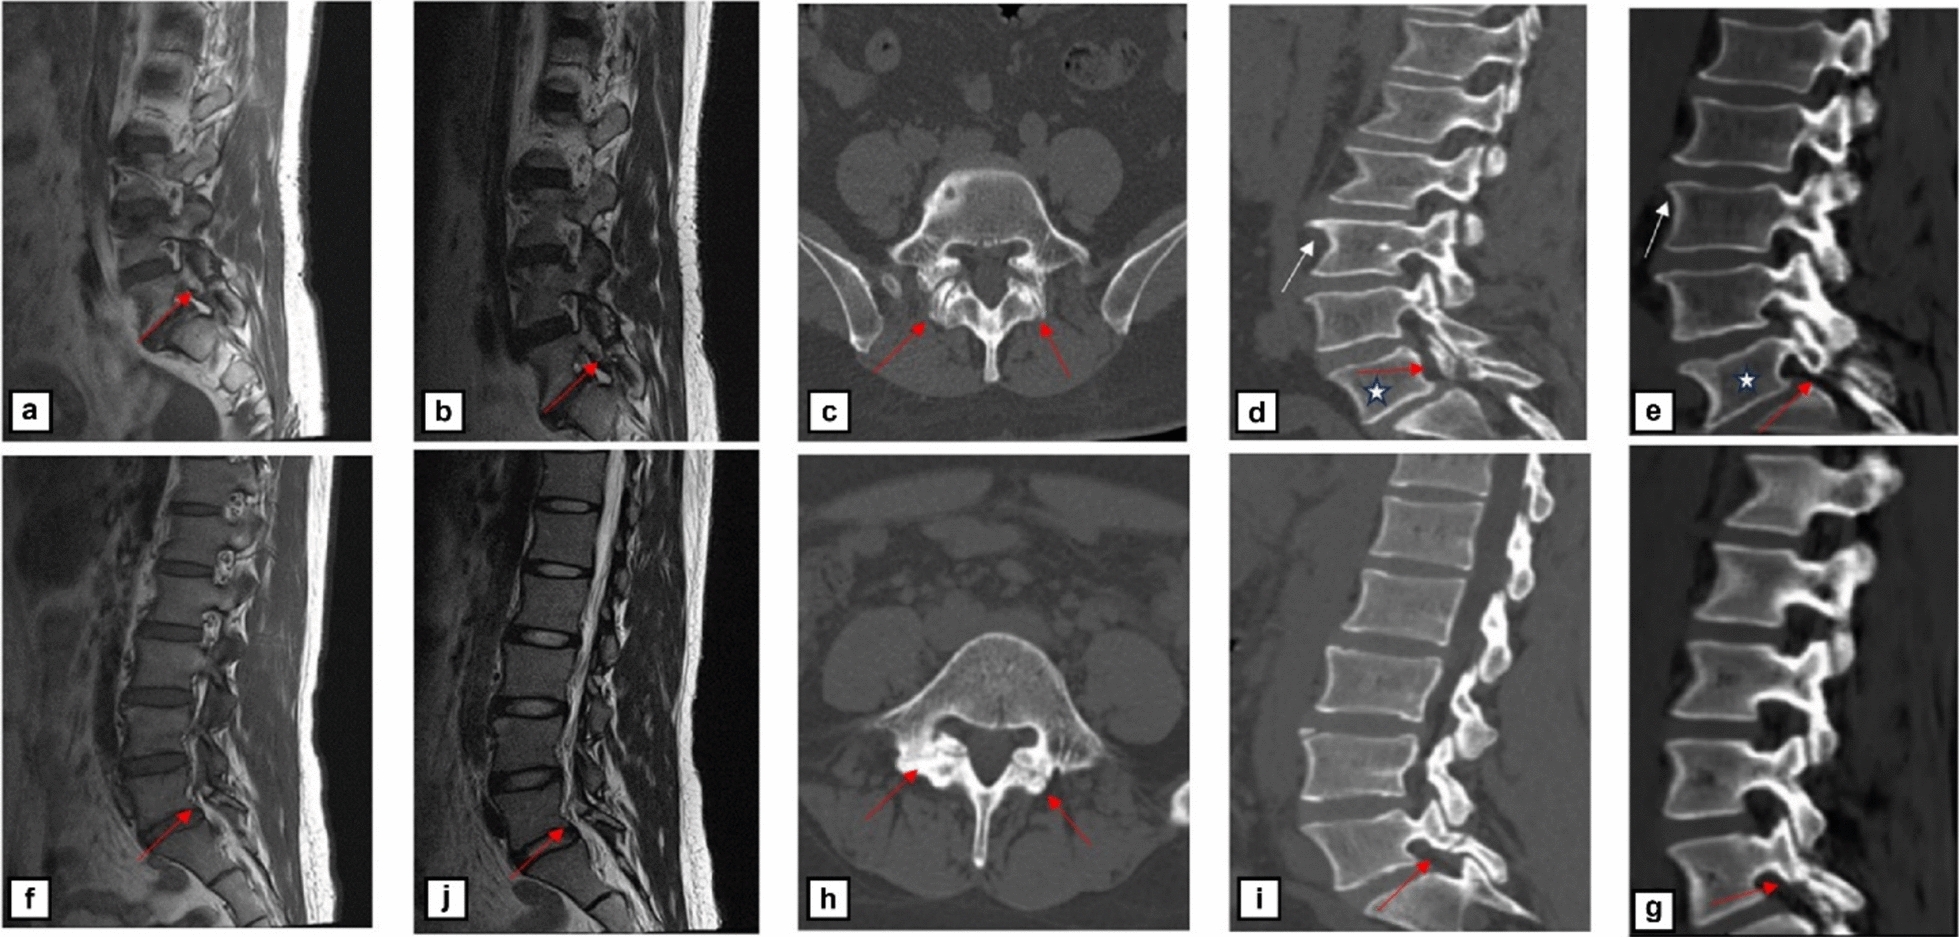

The practical feasibility of sCT for diagnosing lumbar spondylolysis lesions in the lumbar arch was confirmed in a series of cases. Among all three patients with lumbar spondylolysis, the diagnostic performance of sCT and conventional CT assessments showed marked consistency. Nevertheless, conventional MRI sequences faced challenges in clearly delineating the left-sided lumbar spondylolysis in one patient, highlighting the superiority of sCT over conventional MRI. Both sCT and conventional CT accurately identified the cortical disruption of the pars interarticularis. More importantly, the two modalities demonstrated high concordance in depicting the anatomical morphology of the lumbar spondylolysis. Specifically, they provided equivalent imaging information regarding crucial diagnostic details such as the course of the fracture line, the sharpness of cortical margins, and the presence of surrounding osteosclerosis. The use of sCT obviates the need for ionizing radiation and concurrently provides a pathway for identifying spondylolisthesis, osteophytic sclerosis, and related features within a single scan. Our investigation, which identified vertebral osteophytes and sclerosis in the bilateral L5 lumbar spondylolysis of a 60-year-old patient using sCT, hints at its prospective applicability in diagnosing a wide array of musculoskeletal pathologies. This innovative clinical model promises to yield dual benefits for both patients and practitioners by mitigating radiation exposure and streamlining the clinical workflow.